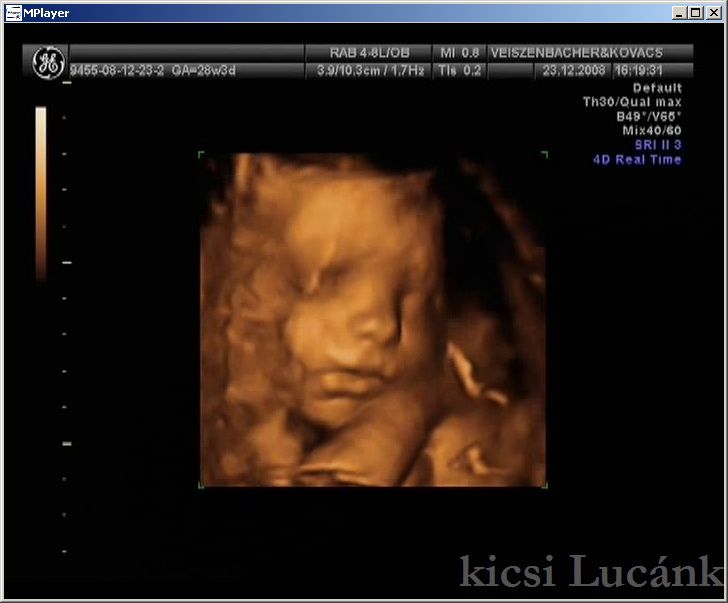

kicsi Lucánk - 2008.12.23 (7 of 13)

luca07